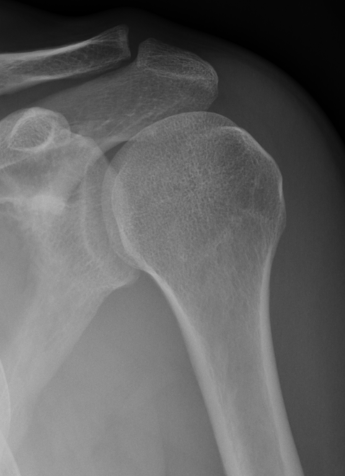

Axillary Xray

Diagnostic - humeral head posterior to glenoid with evidence of reverse Hill Sachs

Reverse Hill Sachs

Humeral head defect

- caused by impaction of anterior humeral head on posterior glenoid

- intra-articular

- measured as a percentage of the articular surface